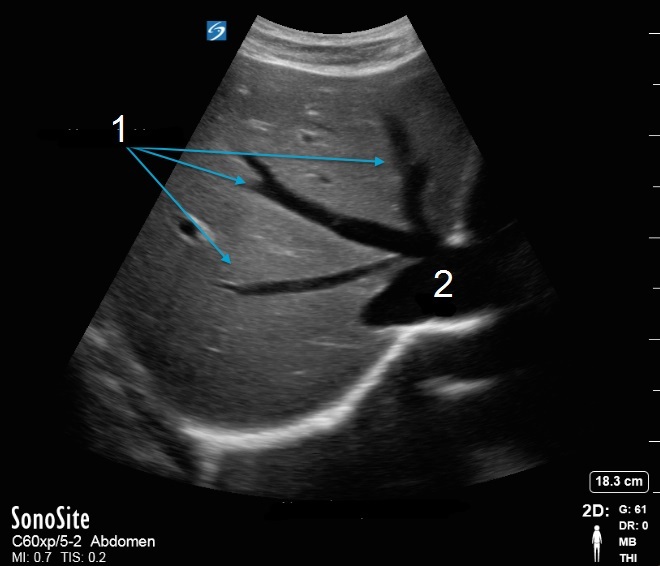

Bild: Leber/Venae hepaticae, transversal

Venae hepaticae

Vena cava inferior (VCI)